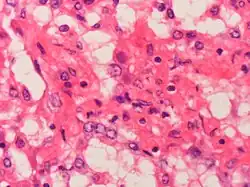

Adenovirus can cause severe necrotizing pneumonia in which all or part of a lung has increased translucency radiographically, which is called Swyer-James Syndrome.[21] Severe adenovirus pneumonia also may result in bronchiolitis obliterans, a subacute inflammatory process in which the small airways are replaced by scar tissue, resulting in a reduction in lung volume and lung compliance.[21]